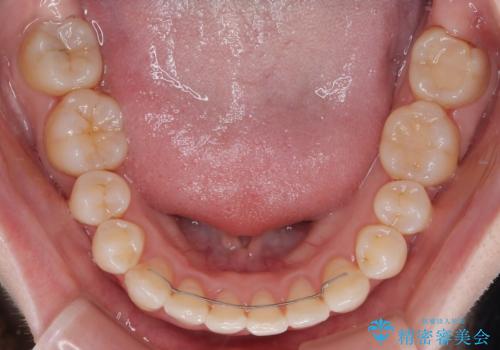

補助装置を併用したおかげで、出っ歯になることなくスムーズに治療を終えることができました。

- 矯正治療後の保定が不十分だと後戻り(元の位置に戻ろうとする動き)をします